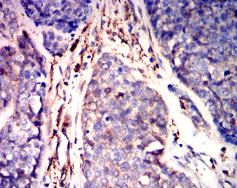

GSN Mouse Monoclonal antibody[5E3B9]

AC2396 GSN Mouse Monoclonal antibody[5E3B9] 100ug $367 10days

Immunogen:    Purified recombinant fragment of human GSN (AA: (673-783)) expressed in E. Coli.

IHC    1/200-1/1000